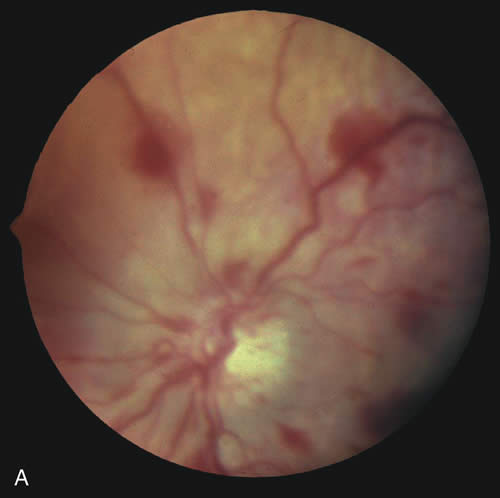

Findings range from a normal fundus to a small number of scattered intraretinal hemorrhages in the posterior pole to massive, confluent hemorrhages from the posterior pole to the ora serrata.(Fig. 10) The hemorrhages may be subretinal, deep intraretinal (dot/blot), nerve fiber layer (flame shaped) or preretinal.19,45 Intraretinal hemorrhages are more common than preretinal or subretinal hemorrhages.32,46 Preretinal hemorrhages must be distinguished from traumatic retinoschisis (see later), which has particular diagnostic significance. White-centered retinal hemorrhages, although classically associated with endocarditis, can occur in any condition that causes retinal hemorrhages, including SBS. Vitreous hemorrhage may be small to massive, and may occur secondary to escape of blood from intraretinal collections or from torn vessels.19 Although vitreous hemorrhage may occur at the time of injury, it may also be a delayed finding occurring 1 to 3 days or more after the initial trauma.47,48

Retinal hemorrhages may be associated with papilledema in SBS. However, papilledema is seen in less than 10% of shaken babies.35, 49 These small, flame-shaped hemorrhages on and radiating around the optic nerve are not necessarily caused by shaking and may be seen in papilledema from any cause. However, retinal hemorrhages associated with SBS may be seen on the optic disc in the absence of papilledema.50

Retinal hemorrhage is usually bilateral but may also be asymmetric or unilateral. Retinal hemorrhage can not be dated with any precision and, therefore, should not be used to help determine when the abusive event occurred.46,47,56,57,58,59 At best, generalizations may be made with wide intervals. For example, intraretinal hemorrhages do not last months, and blood in schisis cavities does not go away in days. Retinal scars or optic atrophy do not form in days.

The differential diagnosis of retinal hemorrhages in a child is vast. However, if one considers a child with the full spectrum of injuries seen in SBS, including brain, skeletal, and eye findings, most would not dispute that the retinal findings are due to nonaccidental injury. However, in a child with a small number of retinal hemorrhages and without retinoschisis, (Fig. 10A) the diagnosis of SBS may be less clear.